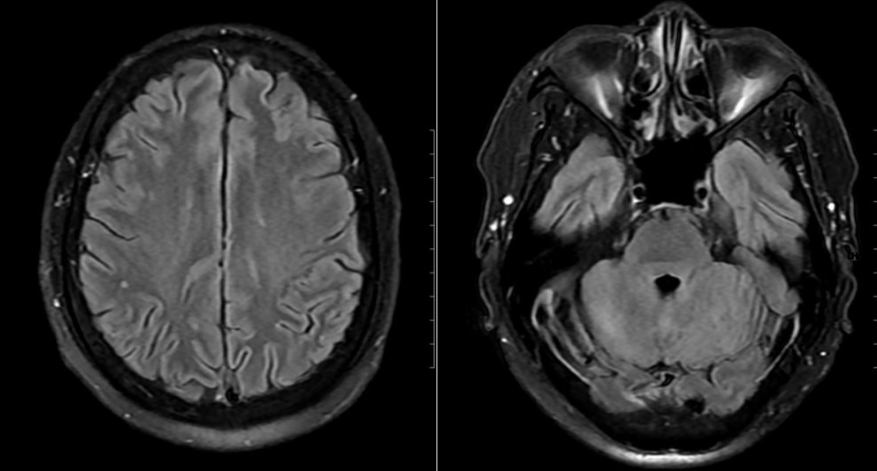

Mặc dù chưa có biểu hiện thần kinh rõ ràng, bệnh nhân vẫn được chọc dò dịch não tủy để loại trừ biến chứng. Kết quả cho thấy dịch não tủy tăng tế bào và protein, phản ứng Pandy dương tính, xác định tình trạng viêm não – màng não. Hình ảnh MRI sọ não còn phát hiện ổ tổn thương nhỏ tại thùy chẩm trái.

Hình ảnh não bệnh nhân có tổn thương.

Từ các dữ liệu lâm sàng và cận lâm sàng, bệnh nhân được chẩn đoán mắc nhiễm khuẩn huyết – viêm não màng não do Streptococcus suis. Ngay khi nhập viện, người bệnh được điều trị kháng sinh đường tĩnh mạch và hiệu chỉnh theo kháng sinh đồ, đồng thời theo dõi sát tình trạng toàn thân và thần kinh.